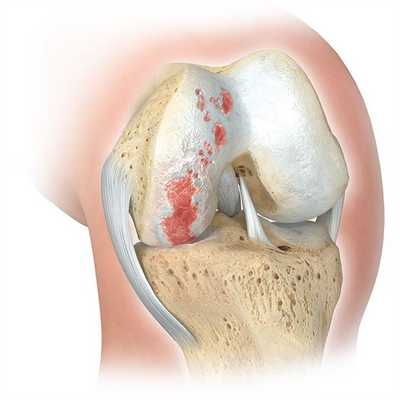

Если сустав поражен указанным на изображении образом, то возможна его частичная замена.

Основной метод лечения - постановка эндопротеза вместо поврежденного сустава. Раньше выполнялось преимущественно тотальное эндопротезирование коленного сустава, однако сейчас активно развивается другое направление - одномыщелковое (частичное) эндопротезирование.